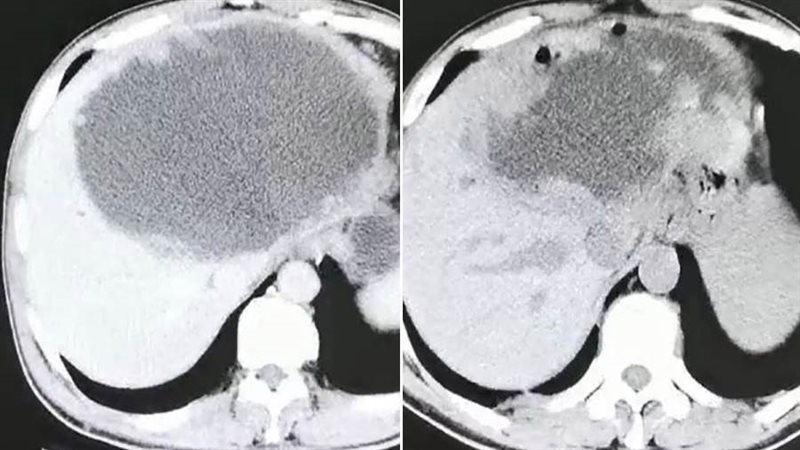

وذهب "شاي" إلى المستشفى بعد أربعة أشهر، عقب معاناته من قشعريرة وحمى شديدة لمدة ثلاثة أيام. وذهل الأطباء عندما اكتشفوا أن كبد المريض يحتوي على كتلة ضخمة مليئة بالصديد يبلغ طولها 19 سم وعرضها 18 سم، وفقا للتقرير. وحاول الجراحون في البداية تقليل النتوء الاجتياحي مثل الكيس، عن طريق تجفيف الكتلة من السوائل، ولكنهم أدركوا بسرعة أن العدوى شديدة جدا، وقرروا قطع نصف الكبد. وكشف فحص لاحق أن الكتلة كانت تحتوي على عدد لا يحصى من البيض الذي وضعه متفرع الخصية الصيني أو وشيعة الكبد الصينية، وهو طفيل موجود في المأكولات البحرية النيئة. واستنتج الأطباء أن "شاي" أصيب بالطفيلي بعد تناول الأسماك غير المطبوخة جيدا أثناء رحلته إلى سيتشوان.